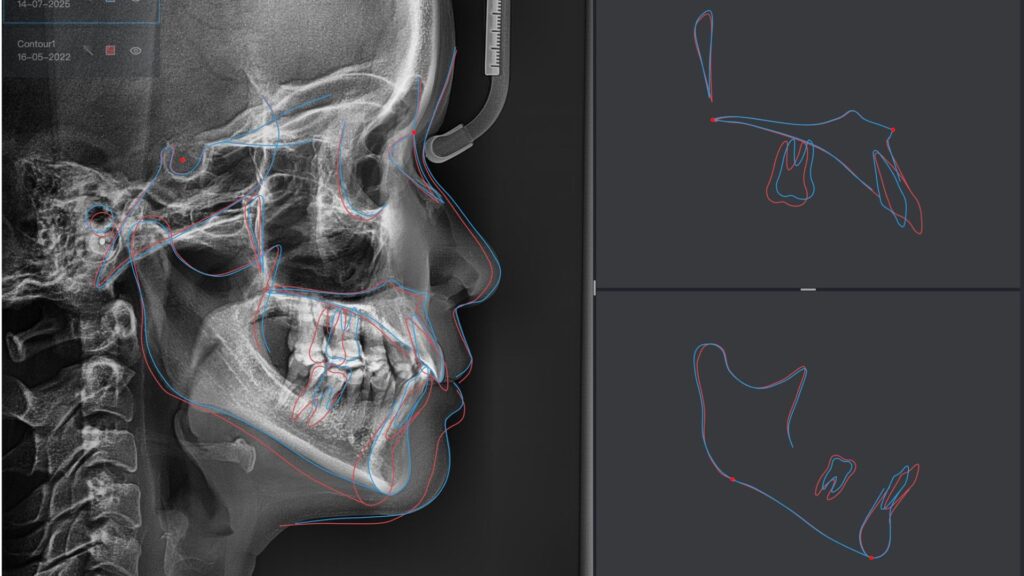

Giảm độ nhô Răng cửa HT 5mm, Giảm độ nhô răng cửa HD 4mm

Mặt nhìn nghiêng phẳng. Giảm độ nhô môi HT, HD 3mm